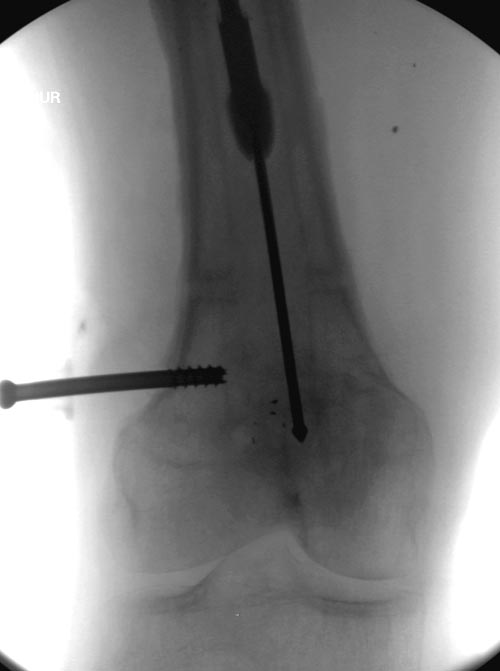

дренирование абсцесса терапевтами. Мы удалили гвоздь, сделали I&D,

рассверливание канала, и ввели гвоздь с антибиотиком. Для гвоздя

использовали стерильную трубку-форму, а антибиотик по 1.0 Tobramycin c

Vancomycin.

В замкнутом без перелома пространстве во время риминга повышается

давление внутри канала, и имеется риск тромбообразования. Для

профилактики и для дренажа - канюлированный винт 6.5 мм в дистальной

части бедра. Обработку заканчивают культурой из раны и канала. Иногда